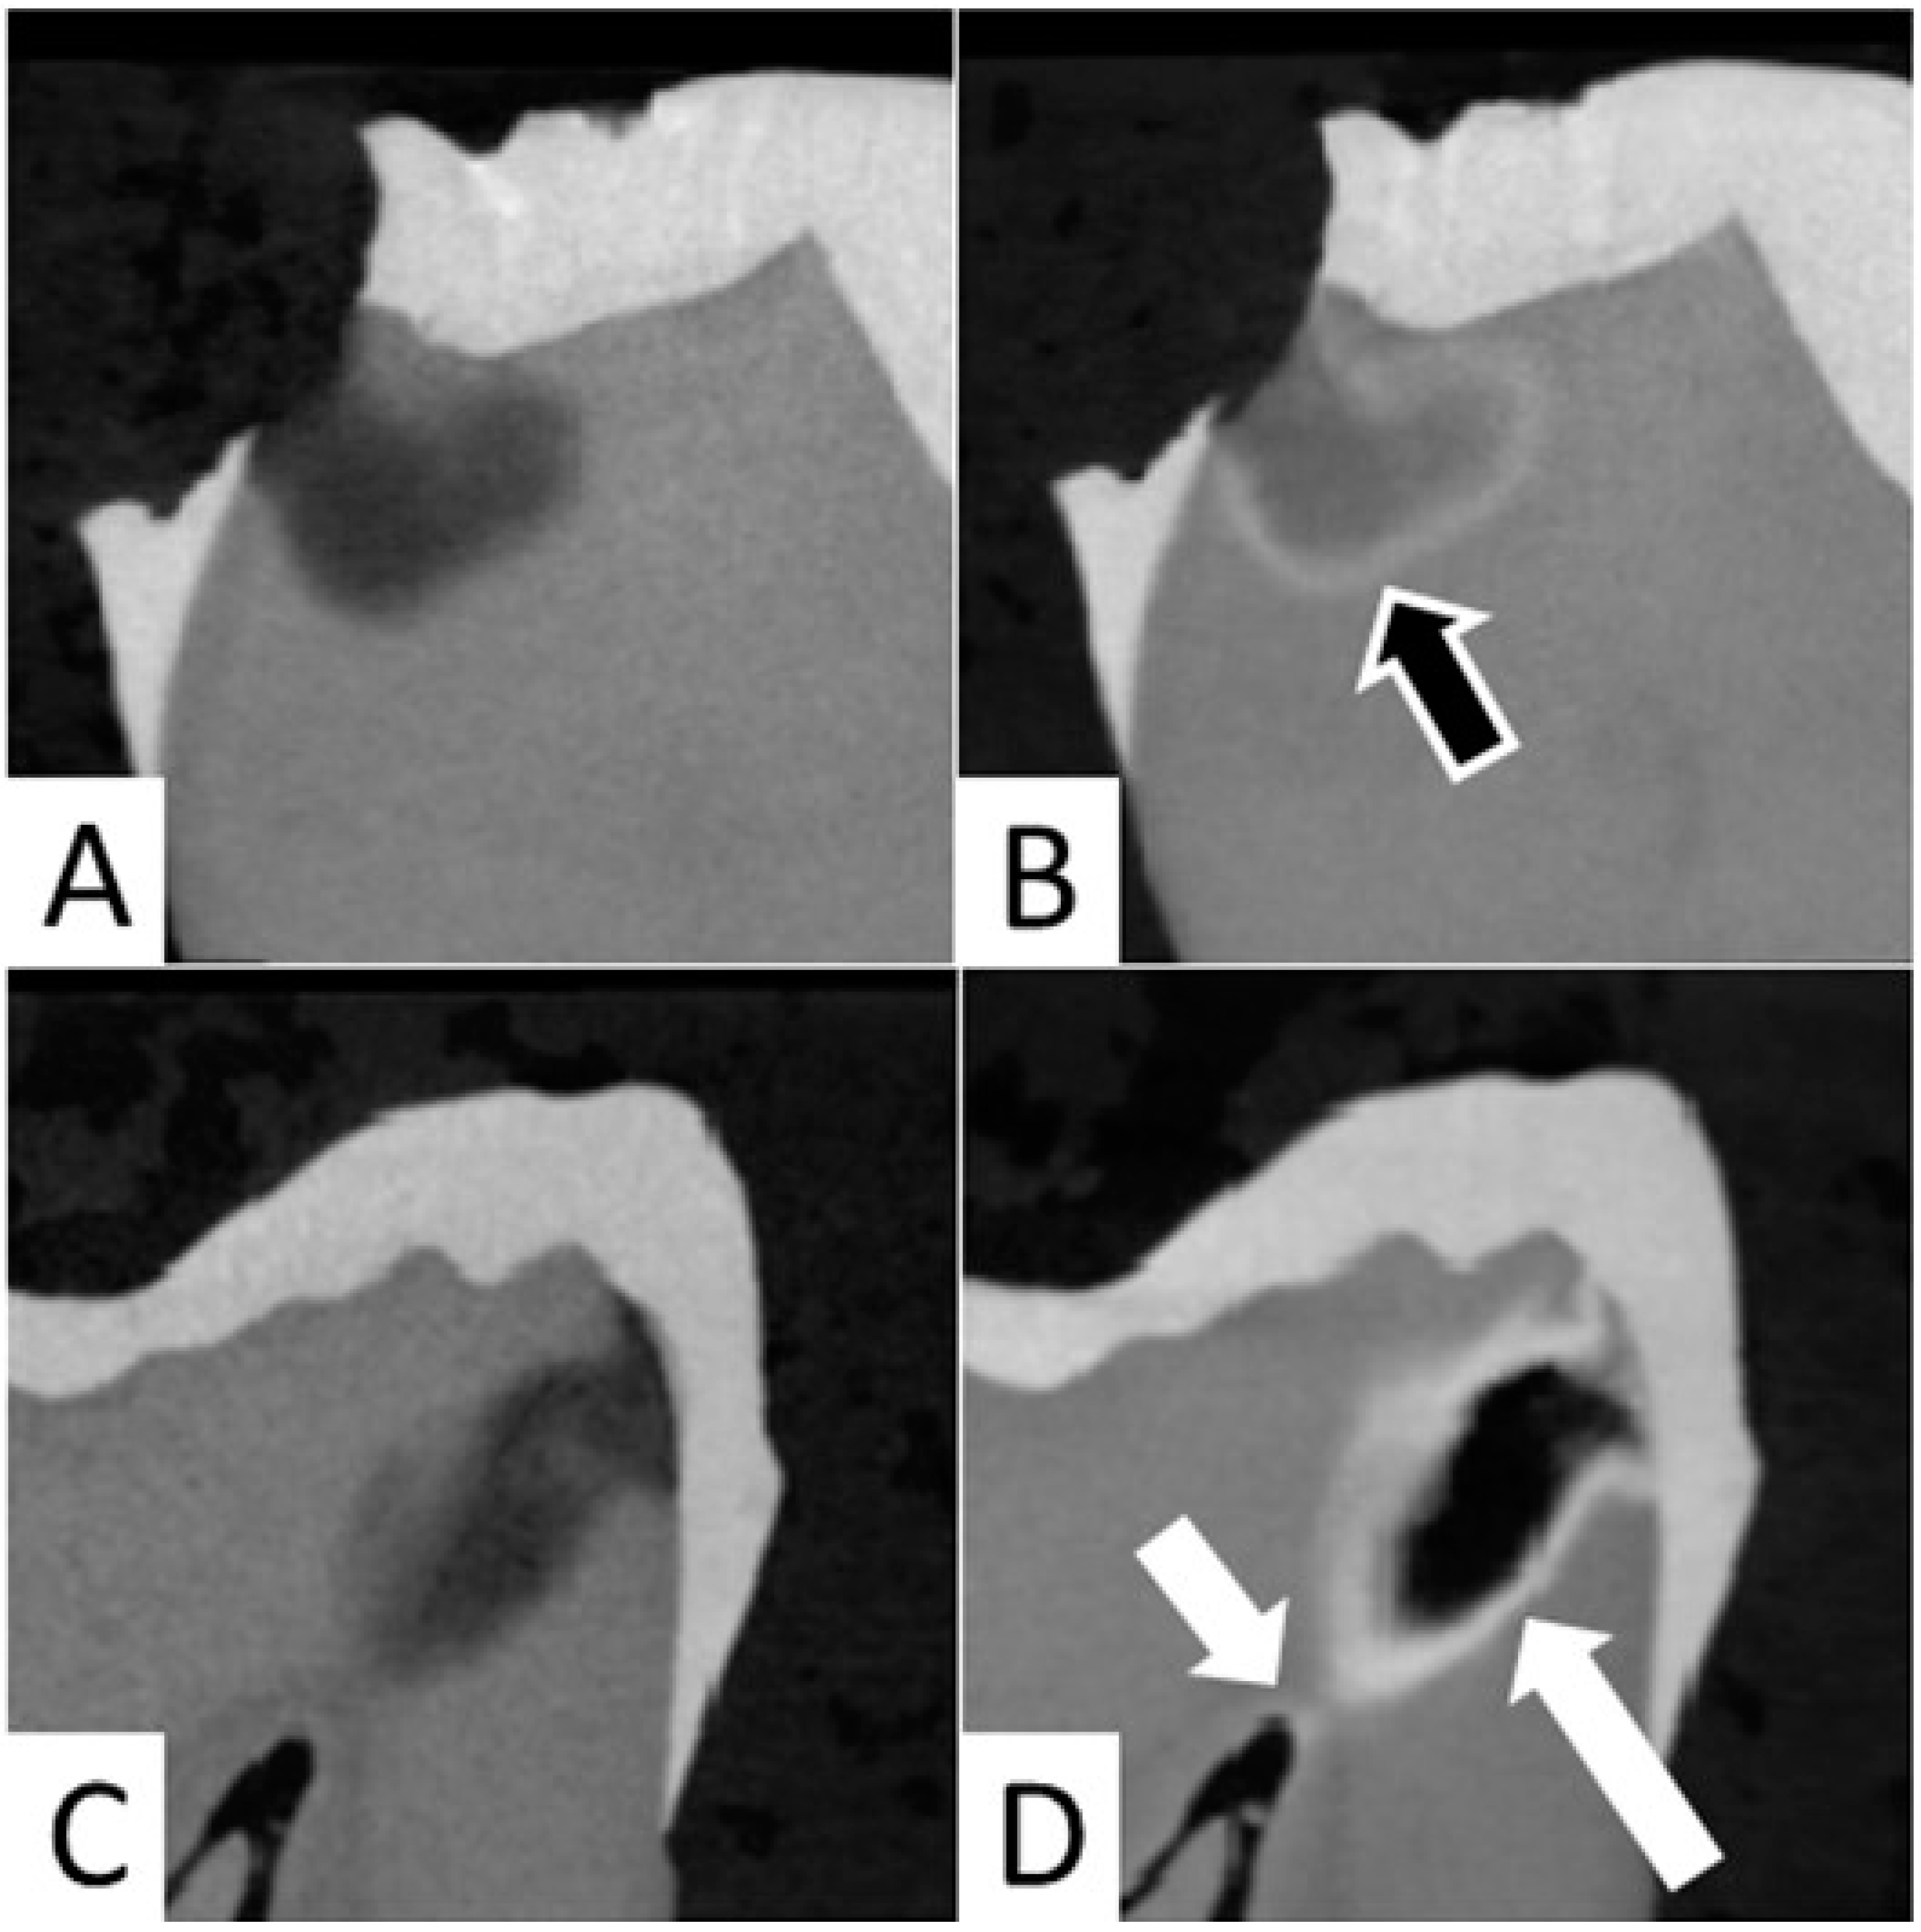

In the current study, it was observed that application of SDF resulted in precipitation of silver at the junction of affected and infected dentin in 12 out of 20 samples (Figure 4A,B). In both groups, the formation of a large aggregation of SDF within the carious lesion was noted in four samples, and SDF reached the pulp chamber in cases of deep caries lesions in eight samples (Figure 4C,D).

Occasionally, SDF seemed to reach the pulp chamber in deep carious lesions (Figure 4C,D). This is consistent with previous observations in primary teeth [13]. Dentin tubules are permeable channels that increase in density and diameter in close proximity to pulp [14,15]. Therefore, application of SDF to deep carious lesions could be associated with risk of SDF traveling through the dentin tubules (Figure 2f) and reaching the pulp chamber (Figure 4D), which could lead to pulpal inflammation and necrosis [16,17,18]. In our study, formation of dentin tubules micro wires could not be distinctly seen on micro-CT possibly due to the lower resolution (12 microns) compared to a prior study (1.3 micron) [19]. However, SDF penetration into dentinal tubules was seen on macro photographs of sectioned teeth (Figure 2f).

In the present experiment, application of SDF and SDF + PI occasionally resulted in large aggregates and very dense radiopaque layers (Figure 4C,D). This might be linked to the characteristics of the carious lesions, although no correlation was found between the presence of large aggregates and the preoperative radiopacity of the carious lesions (data not shown). Consequently, we opted to present the results as median and interquartile range to limit the impact of extreme values. In addition, although no significant difference was found when comparing the distribution of our data to normal distribution, we opted to report the results of non-parametric tests instead of the ANOVA repeated measures, as the Mauchly’s test of Sphericity tended to be statistically significant (Group 1 p = 0.077, Group 2 p = 0.089), which could violate the test assumptions. Regardless, similar results were obtained when using the ANOVA repeated measures and Wilcoxon Signed Rank Test with Bonferroni adjustment for multiple comparisons.

Figure 4. (A,B) Micro-CT images showing precipitation of SDF at the junction of affected and infected dentin (outlined arrow). (A) Preoperative image and (B) after SDF application. (C,D) Micro-CT image showing aggregation of SDF (white long arrow) and penetration of the SDF to the pulp chamber (short white arrow) (C) Preoperative image and (D) after SDF application.